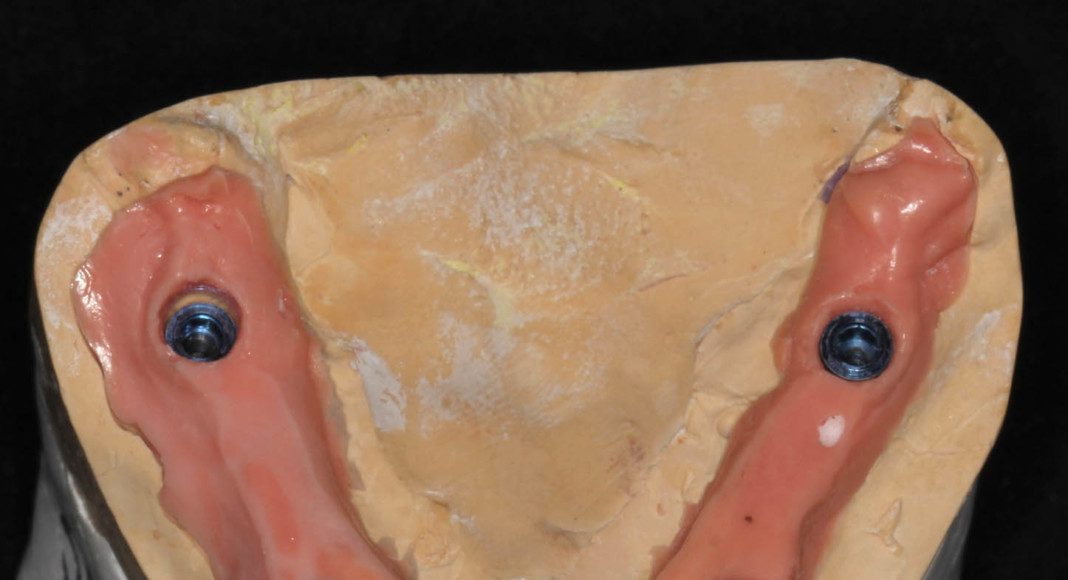

Lower zirconia bridge, off the master cast. This is the intaglio (tissue side) of the prosthesis. Note that is flat to convex for easy cleaning.